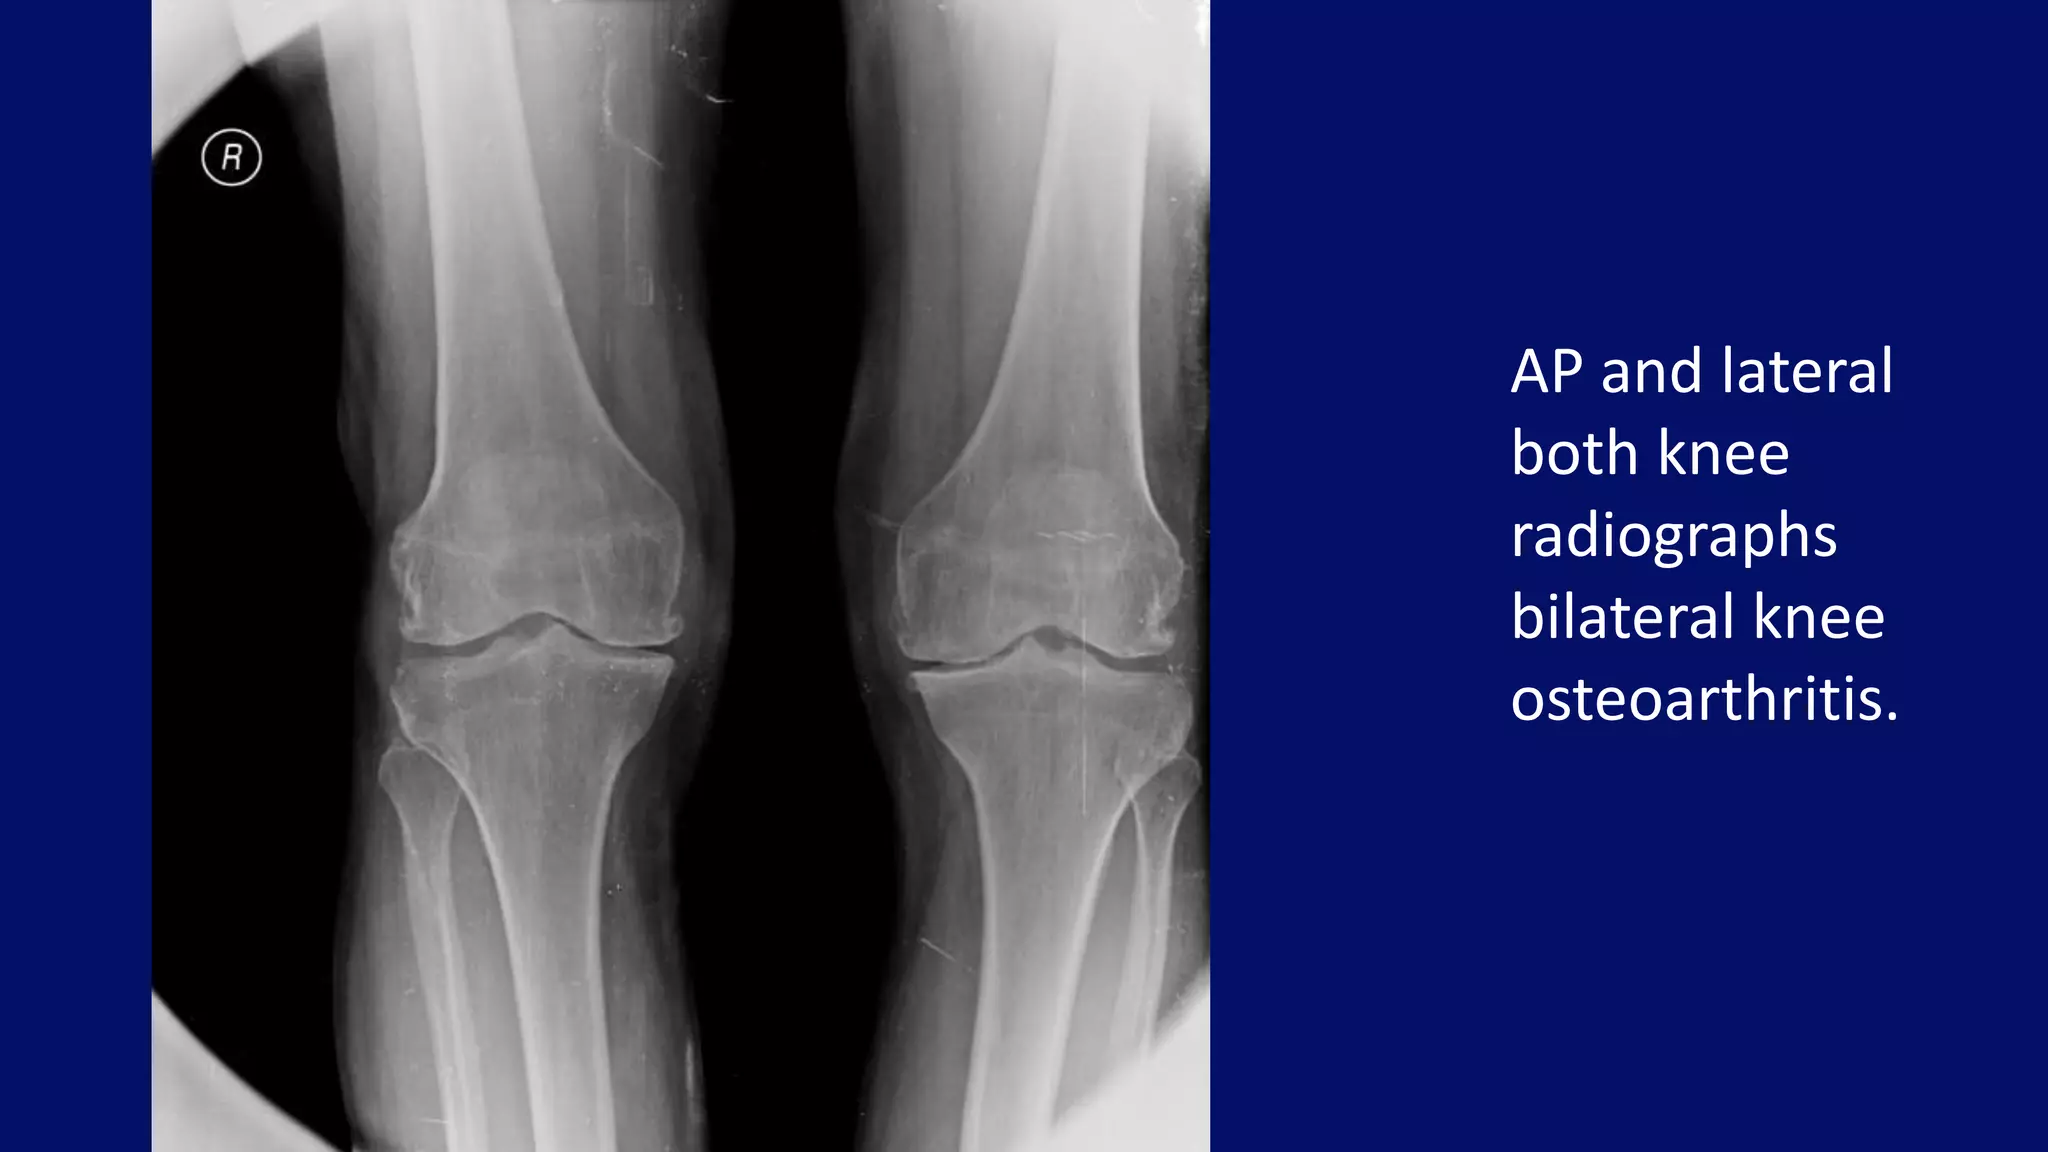

Osteoarthritis of left knee

L L

AP and lateral

both knee

radiographs

bilateral knee

osteoarthritis.

• #23 Anteroposterior (A) and lateral (B) projections of the knee of a 57-year-old woman demonstrate narrowing of the medial femorotibial and femoropatellar compartments, subchondral sclerosis, and osteophytosis, which are the typical features of osteoarthritis. Note that osteophytes that were not obvious on the frontal projection are much better-demonstrated on the lateral radiograph.